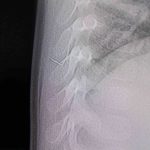

Alınan bilgiye göre, Kahramanmaraş’ta farklı ortopedi, çocuk cerrahisi ve beyin cerrahisi kliniklerine başvurusu yapılan bir yaşındaki bebeğin, sırt bölgesinde yabancı bir cisim olduğu ancak müdahalenin zor olduğu ve 8 yaşına kadar beklenmesi gerektiği bildirildi. Aile, bebekleri için son olarak HG Hospital’e başvurdu. HG Hospital Beyin ve Sinir Cerrahisi Uzmanı Prof. Dr. İdris Altun tarafından yapılan tetkiklerde, yabancı cismin cilt altında, omurilik kanalına yakın bir bölgede olduğu ve akciğer zarına doğru ilerlediği belirlendi. Hasta, genel anesteziye alınmadan, lokal anestezi ve sedasyon eşliğinde ameliyata alındı. Yapılan müdahalede yabancı cisim tamamen çıkarıldı. Çıkarılan cismin, ince zımba teline benzer metal bir tel olduğu ve yaklaşık 2 santimetre uzunluğunda bulunduğu tespit edildi. Hasta, aynı gün taburcu edildi.

Konuya ilişkin açıklama yapan Prof. Dr. İdris Altun, “Sırtında yabancı bir cisim olduğu söylenmiş ancak çıkarılamayacağı ve 8 yaşına kadar beklenmesi gerektiği ifade edilmişti. Bize başvurduğunda yaptığımız tetkiklerde, cilt altında, omurilik kanalına çok yakın ve akciğer zarına doğru ilerleyen bir yabancı cisim tespit ettik. Hastamızı tamamen uyutmadan, lokal anestezi ve sedasyon eşliğinde müdahale ederek lezyonu tamamen çıkardık. Çıkardığımız cismin ince zımba teline benzer, yaklaşık 2 santimetre uzunluğunda metal bir tel olduğunu gördük. Bu yabancı cisim alınmasaydı, bölgede enfeksiyon gelişebilirdi. Enfeksiyon sonucu omurilik kanalında ciddi hasarlar oluşabilir, çocuk büyüdükçe cismin hareket etmesine bağlı olarak omurilikte zedelenmeler meydana gelebilirdi. Ayrıca yana doğru ilerleyerek akciğer zarına ve akciğere batma riski vardı. Bu da enfeksiyona ve ilerleyen süreçte tümörle karışabilecek tablolara neden olabilirdi. Şu an hastamız gayet sağlıklı. Gerekli kontrolleri yaptık ve aynı gün taburcu ettik” dedi.